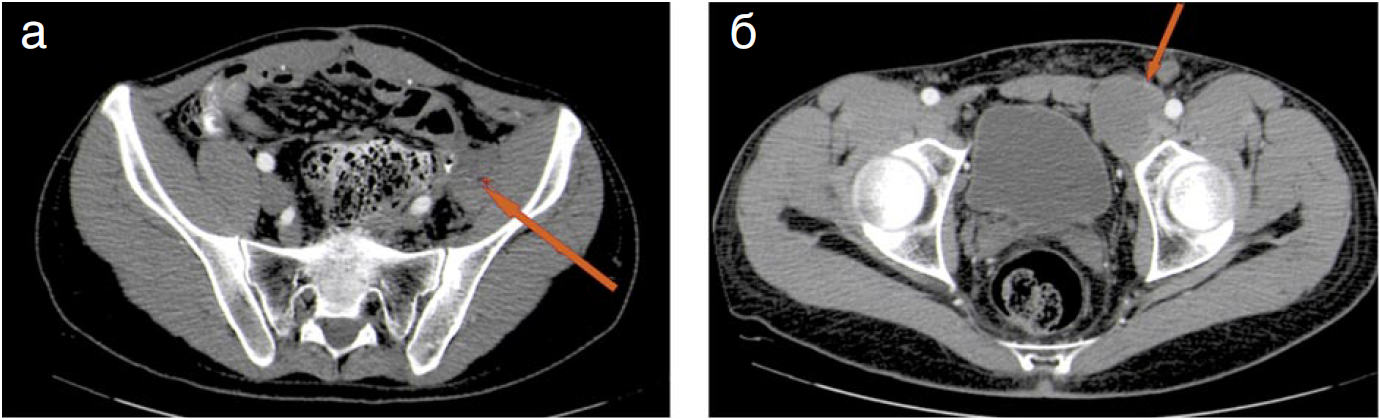

Через 7 мес выявлен 3-й рецидив опухоли. На мультидисциплинарном обсуждении, учитывая отсутствие жалоб и небольшие размеры рецидивной опухоли, а также отсутствие риска развития угрожающих жизни осложнений решено ограничиться наблюдением.

Больному проводится ежегодное обследование с частотой один раз в полгода – данных по поводу роста рецидивной опухоли не отмечено. На сегодняшний день больной жив, жалоб не предъявляет, трудоспособен, постоянно контактирует с группой врачей ФГБУ «НМИЦ онкологии им. Н.Н. Блохина».